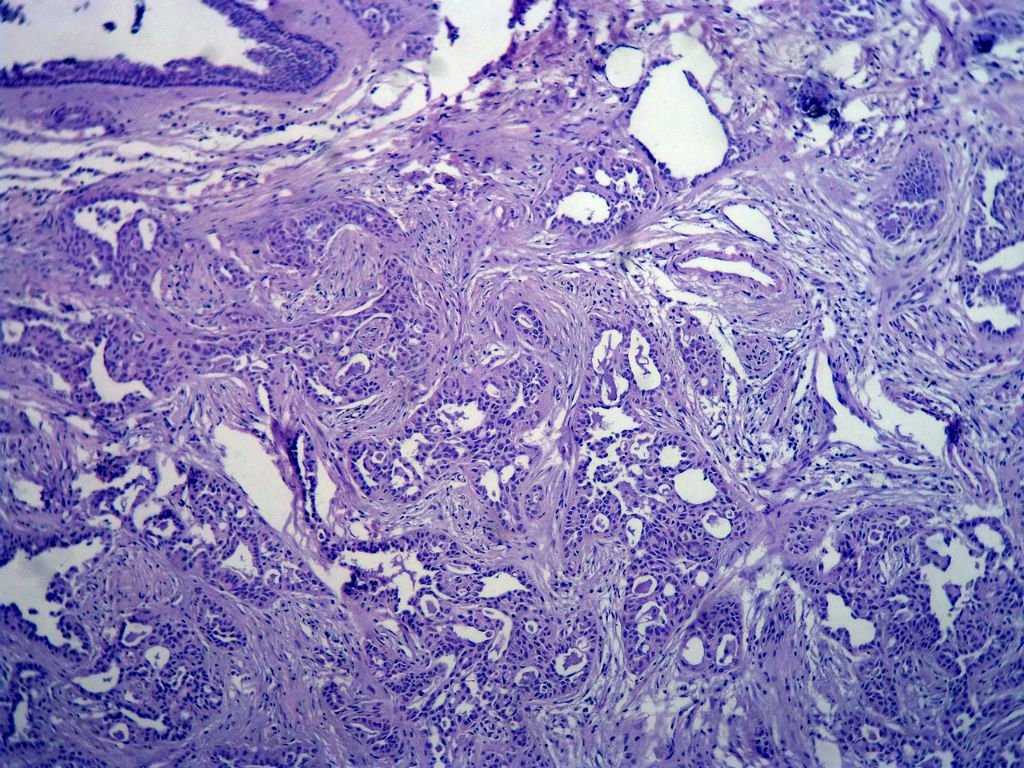

本例太完美了,也非常惊险,真的,至少在我们中国的这个病理环境下能做到这样真心不错。这是个罕见病例,居然冰冻让你碰上了,从冰冻——常规——IHC都完备。我从冰冻看到常规未看免疫组化之前还一直犹豫是不是癌?是癌但一定是您说的分泌性癌吗?看常规时只是觉得浸润性癌够了,后来看到常规的筛状结构+分泌物才确定形态学也够了,就差IHC了,结果您贴出来上级医院的IHC结果真的是3阴,S-100+,高分子量CK部分+,这个表达模式完全符合分泌性癌(我也遇到一个分泌性癌,IHC表达方式完全和您的这例一样),当然必须是结合形态学了。

这个癌既符合3阴乳腺癌,又符合基因上分类的基底细胞样乳腺癌,只不过预后很好,和一般意义上的3阴乳腺癌、基底细胞样乳腺癌不一样!如果有条件再做下FISH检测到ETV6重排那就更完美了

Secretory breast carcinomas (o0.15% of breast tumors) are associated with a characteristic morphology and a

favorable prognosis. Remarkably, this entity is the only epithelial tumor of the breast with a balanced

translocation, t(12;15), that creates an ETV6-NTRK3 gene fusion encoding chimeric tyrosine kinase also

encountered in cellular mesoblastic nephroma and infantile fibrosarcoma. The aim of this study was to

determine the phenotypic class (ie luminal A/B, ERBB2, basal-like) of secretory breast carcinoma. A series of six

secretory breast carcinomas were identified in our files. The ETV6 rearrangement was confirmed in all cases by

fluorescence in situ hybridization. Immunophenotype was assessed with anti-ER, PR, ERBB2, KIT, EGFR,

E-cadherin, vimentin, PS100, smooth muscle actin, basal (CK5/6 and 14), luminal cytokeratins (CK8/18) and p63

antibodies. In situ and invasive components shared the same immunoprofile and were ER, PR, ERBB2 negative

with expression of basal cytokeratins. ETV6 gene alterations were present in both in situ and invasive

components, highlighting their genetic similarities. The immunoprofile data (triple-negative with expression of

basal markers) showed that secretory breast carcinomas with ETV6-NTRK3 fusion gene belong to the

phenotypic basal-like spectrum of breast carcinomas. These results support the hypothesis that secretory

breast carcinomas have immunohistochemical and genetic features that distinguish them from other basal-like

tumors of the breast.